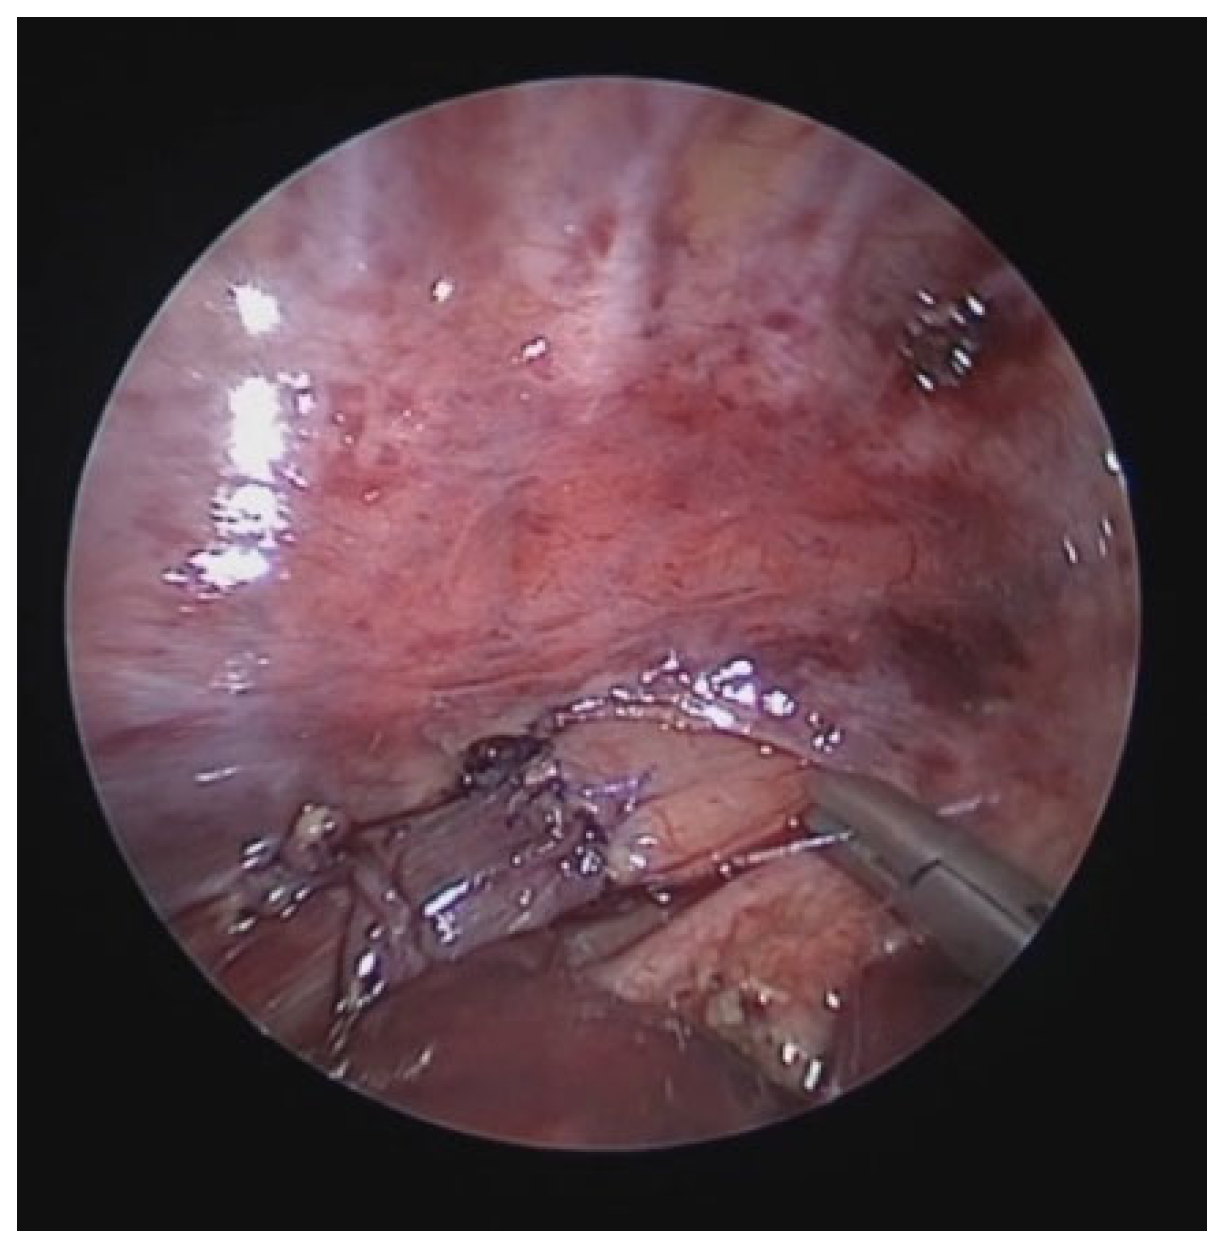

Figure 11.

Intraoperative VBS during OAA (after thymectomy): A) without traction on the aortic arch; B) significant increase in tracheal lumen while traction is exerted on the aortic arch. Abbreviations. VBV: Videobronchoscopy; OAA: Open Anterior aortopexy.

Despite the surgery, with favorable intraoperative control, the patient continued to experience recurrent cough, frequent need for antibiotic therapy cycles, repeated emergency room visits, and four hospitalizations for asthmatic bronchitis requiring HFNC.